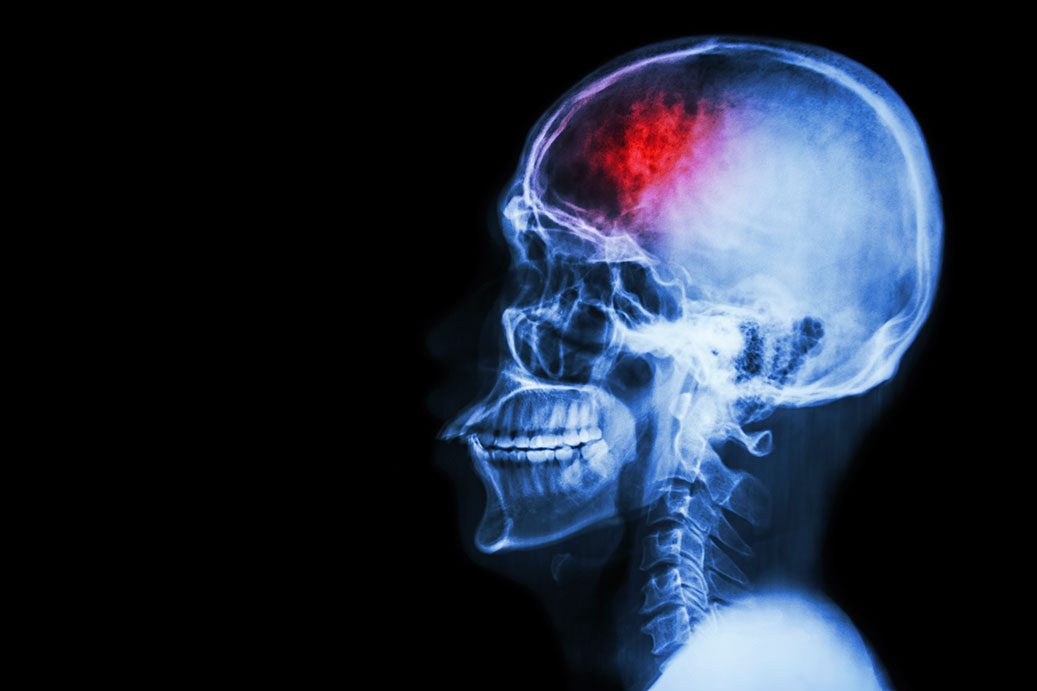

Анатомия мозга: Рентгеновские снимки для презентаций